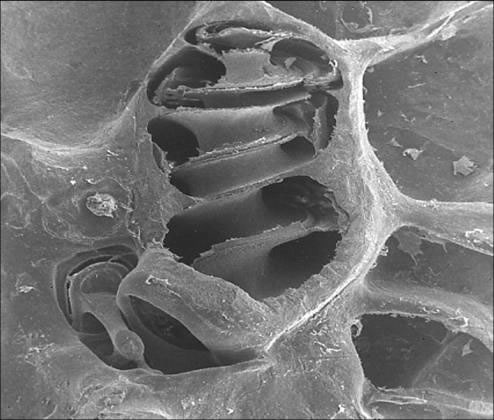

GFD/kohlea.jpg